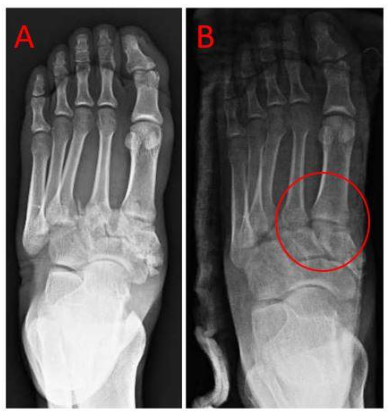

Patients presenting with midfoot dislocations in the acute setting were included in this study. Initial examination was performed on the affected foot to evaluate for any soft tissue compromise or presence of underlying peripheral vascular disease (PVD). The use of this technique is contraindicated in the setting of any digital neurovascular compromise or PVD. No numerical data was collected in this study; instead, the success of the reduction technique was assessed qualitatively through radiographic evaluation of post-reduction imaging. As evidenced by post-reduction films, the anatomic alignment of midfoot joints served as the primary measure of success using the modified Quigley technique.

Utilization of this method has resulted in acceptable reduction of Lisfranc joint fracture/dislocations performed in the acute setting. Traction applied at the second digit allows for axial traction along the second metatarsal due to the stout ligamentous attachments at the metatarsophalangeal joint level. This, in turn, provides distraction of the dislocation at the tarsometatarsal level and allows re-nesting of the “keystone” of the midfoot by relocating the second metatarsal base between the medial and lateral cuneiforms. This allows for expedited stabilization of the Lisfranc or midtarsal joints while minimizing complications and soft tissue compromise. This reduction technique may be applied to many specialties to improve the quality of acute midfoot and metatarsal fracture reduction in daily practice including those in trauma, emergency medicine, orthopedics, and podiatry.

After immediate reduction and stabilization, nearly all Lisfranc injuries require operative treatment for definitive fixation. This, in turn, limits our long-term follow-up as to the quality of the initial reduction. However, we were able to devise that an initial reduction to near anatomic alignment showed no incidence of soft tissue or neurovascular compromise. In regard to forefoot fracture without midfoot involvement, axial traction applied to the distal aspect of the foot may allow for the reduction of shortened and displaced metatarsal fractures with this same method.